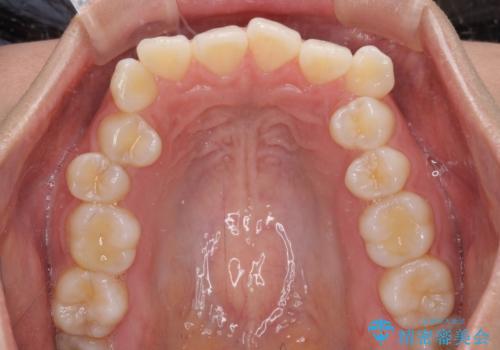

- 前歯のデコボコを治したいとのことで来院された患者様です。

上下顎ともに歯列全体の後方移動とIPR(歯と歯の間を削る)によってデコボコが解消するように設計し、インビザラインにより治療を行うこととしました。

上下ともにIPRを積極的に行っているため、舌の突出癖をしっかりと改善できないと、後戻りにより隙間やデコボコが早い段階で発現することになるため、舌のトレーニングが非常に大切になります。